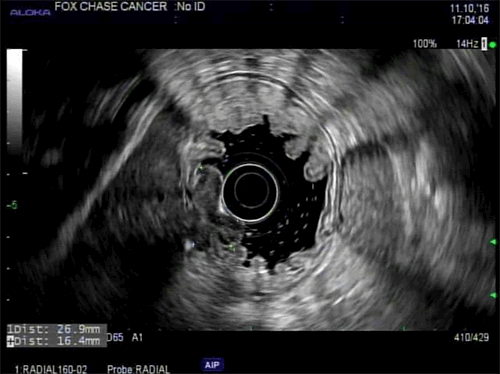

We report a case of colorectal metastases to the gastric mucosa approximately 3 years after resection of the primary tumor. Our patient was a 71-year-old male with a history of stage IIIB, pT3N1cM0 moderately differentiated adenocarcinoma of the transverse colon status post laparoscopic transverse colectomy on January 28, 2013, followed by adjuvant FOLFOX administered between March 2013 and August 2013. On surveillance imaging in March 2014, he was found to have a solitary FDG-avid left hepatic lobe lesion confirmed to be a hepatic colorectal metastasis on US-guided FNA. He underwent partial left hepatic lobectomy on April 2014. He subsequently received continued cancer surveillance with periodic imaging, colonoscopy, and serum carcinoembryonic antigen (CEA) levels with no evidence of disease. In particular, his CEA prior to the colectomy was 0.8 ng/ml and prior to his gastrectomy was 1.4ng/ml, therefore his tumor was not a CEA producer. In October 2016, he presented with fatigue, 16 pound weight loss, shortness of breath, and anemia. As before, his CEA remained within normal limits. He underwent an EGD which revealed a 3 cm, raised, fungating mass with a central depression in the gastric body along the lesser curvature just above the incisura (Figure 1). Subsequent EUS was consistent with a 27 mm, uT2-3N0 tumor (Figure 2).

Figure 1. EGD revealed a 3 cm, raised, fungating, mass with central depression (“bull’s eye sign”, yellow arrow) in the gastric body along the lesser curvature just above the incisura.

At EGD, gastric mucosal metastases can usually be categorized into one of three categories based on their endoscopic features: non-ulcerated masses, submucosal masses with ulceration at their apex, or multiple nodules of varying sizes with ulceration.7,8 Some reports have described a characteristic “bull’s eye sign”, or a raised lesion with central depression.9,10 In a series from the National Cancer Center Hospital in Tokyo composed of 54 patients with gastric mucosal metastases and 347 autopsy cases, the majority of tumors were solitary (65 percent) versus multiple (35 percent).1 In addition, the majority of lesions were located in the middle or upper thirds of the stomach.1 Our patient had a solitary, fungating mass with a central depression located along the lesser curve in the mid-body. Lesions can also appear as polypoid masses ulcers, ulcerated protruding lesions, or thickening of the gastric wall.7,11 Of note, the primary tumor type may dictate the endoscopic features of the gastric mucosal metastasis. For example, gastric mucosal metastases from melanoma may appear as melanotic nodules or as masses with necrosis and melanosis on EGD.12